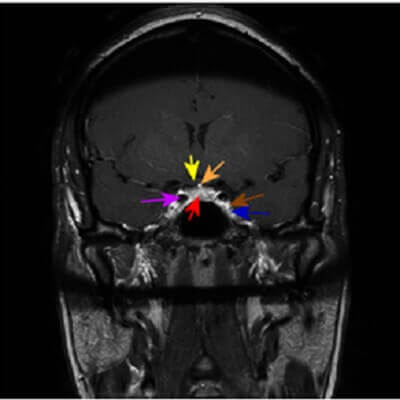

Figure 1: Some basic cavernous sinus region anatomy, with arrow color designated in brackets. Cavernous sinus (blue), optic chiasm (yellow), pituitary gland (red), infundibulum (orange), cavernous carotid (purple), intra cavernous portion of cranial nerves 3-5 (brown).

The cavernous sinus also contains several critical structures – the internal carotid arteries, cranial nerves 3, 4, 6 and the first two branches of 5. Most of the cranial nerves run along the wall of the sinus which is formed by dural reflections at the skull base. Only cranial nerve 6 runs within the cavernous sinus and as such is the most likely nerve to be affected by cavernous sinus pathology.